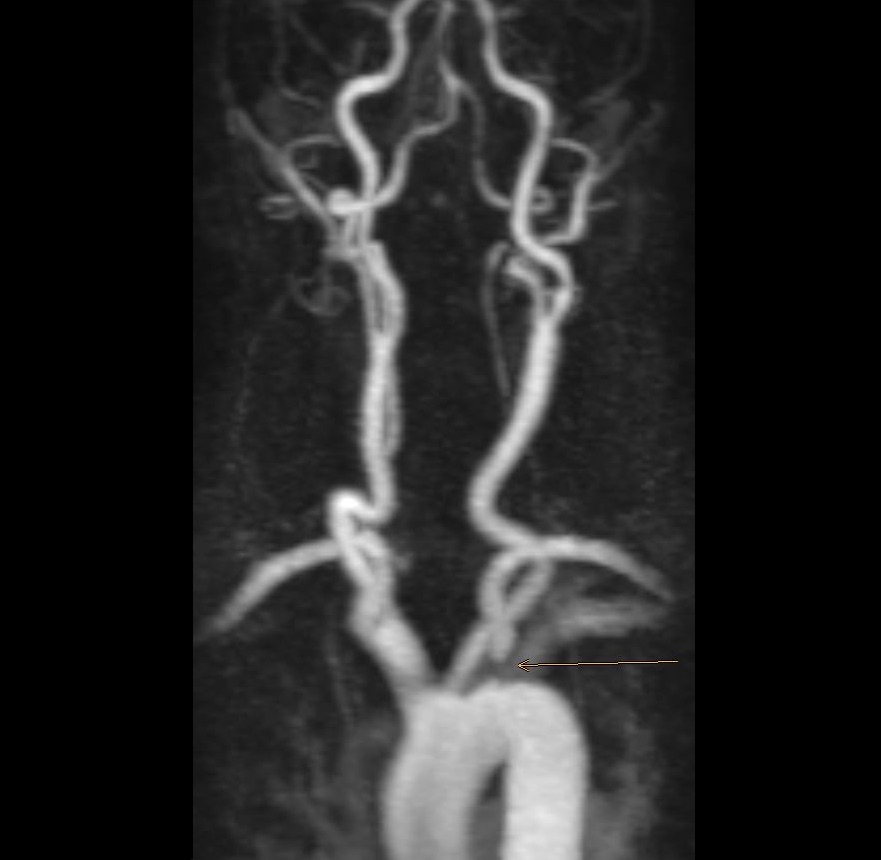

Engstellen (Stenosen) der hirnversorgenden Gefäße sind meist Folge einer Arteriosklerose. Sie können zu Schlaganfällen führen, wenn

Solche Engstellen sind - wie die Arteriosklerose - sehr häufig und müssen nicht zu Beschwerden führen: sogenannte asymptomatische Stenosen. Mitunter werden sie bei Untersuchungen des Gehirns mit Kernspintomographie oder Ultraschall gefunden.

Die interventionelle Therapie von Stenosen erfolgt über einen Gefäßkatheter, der meist von der Leiste oder vom Arm bis in den Halsbereich vorgeschoben wird. Dort kann mit Hilfe eines Ballons die Engstelle zunächst aufgedehnt und dann mit einer Gefäßstütze (Stent) stabilisiert werden.

Solche Eingriffe sind - ebenso wie die Operation - nicht risikofrei. Umso wichtiger ist uns, dass wir die PatientInnen sorgfältig, besonnen und mit viel Zeit beraten. Wir nutzen dabei die Informationen von PatientInnen und ihrer Vorgeschichte, die körperliche Untersuchung, Ultraschall, CT und MRT gleichermaßen, um die Risikoabwägung zu treffen.